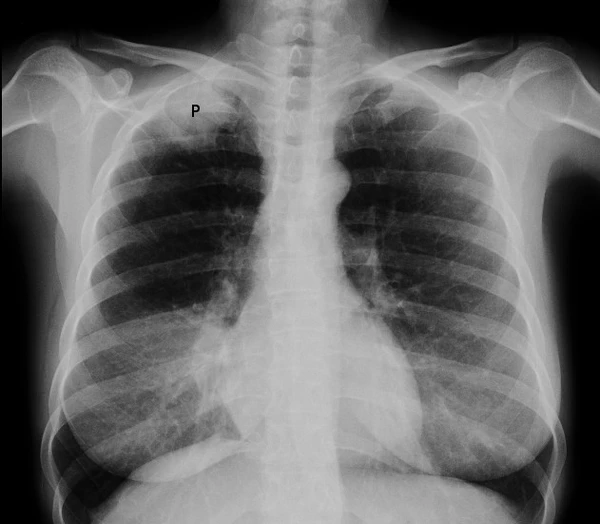

Рак верхушки лёгкого с синдромом Панкоста

Опухоль Панкоста или опухоль верхней борозды лёгкого (это название чаще употребляется в англоязычной литературе) — рак первого (верхушечного) сегмента лёгкого с синдромом Панкоста.